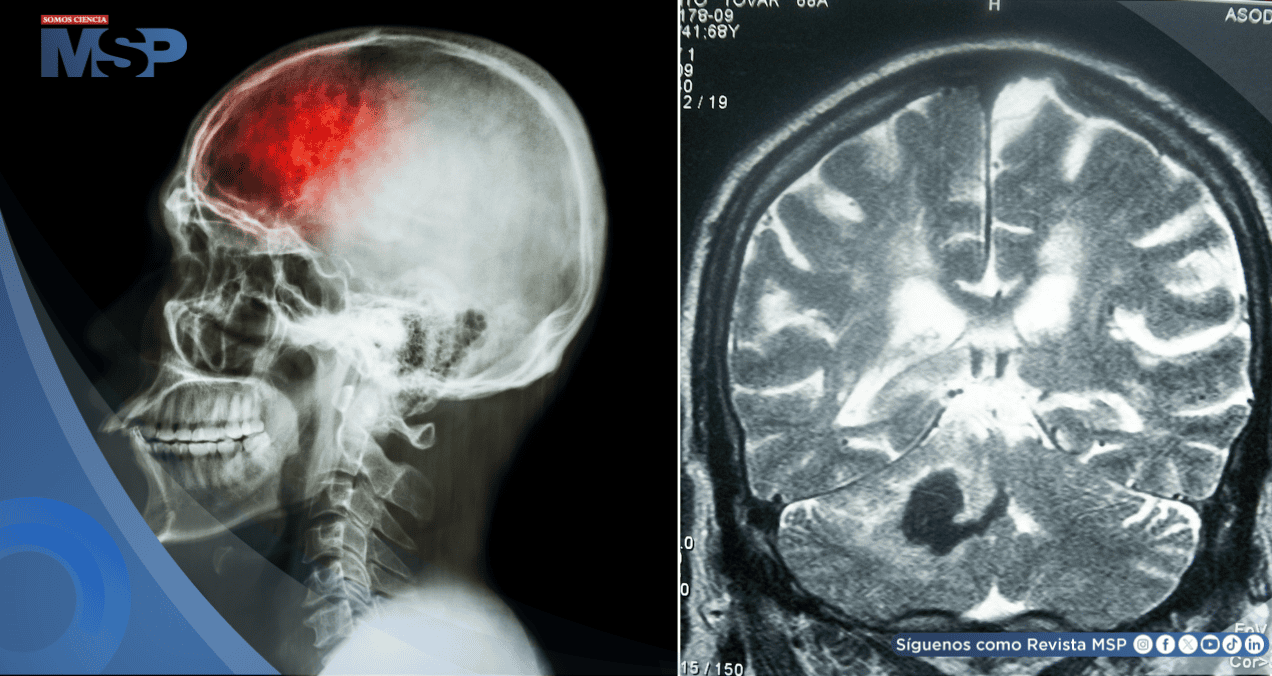

Para diferenciar un ictus verdadero de un "mimic", la herramienta fundamental es una historia clínica detallada y una exploración neurológica minuciosa. "Existen casos, por ejemplo, como las migrañas hemipléjicas antes citadas, en los que se hace necesario realizar una neuroimagen (RMN o resonancia magnética) para llegar al diagnóstico seguro", apunta la experta.